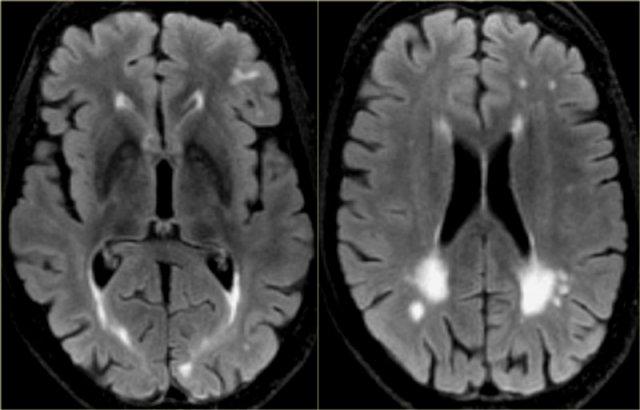

Bệnh Angiopathy Amyloid Não (CAA)

Sa sút trí tuệ có thể là biểu hiện lâm sàng trong CAA, một tình trạng trong đó β-amyloid lắng đọng trong thành mạch máu của não.

Hậu quả là xuất huyết, thường là vi xuất huyết, nhưng cũng có thể xảy ra xuất huyết dưới nhện hoặc tụ máu thùy não.

Trên MRI, chuỗi xung T2* sẽ cho thấy nhiều vi xuất huyết, điển hình ở vị trí ngoại vi (trái ngược với vi xuất huyết do tăng huyết áp, thường nằm ở vị trí trung tâm hơn, ví dụ ở hạch nền và đồi thị).

Ngoài ra, FLAIR sẽ cho thấy tăng tín hiệu chất trắng mức độ vừa đến nặng (Fazekas độ 2 hoặc 3)

Hình ảnh T2* ở bệnh nhân CAA cho thấy nhiều vi xuất huyết nằm ở ngoại vi.

Hình ảnh FLAIR của cùng bệnh nhân cho thấy tăng tín hiệu chất trắng Fazekas độ 2.

Hình ảnh T2* ở bệnh nhân có vi xuất huyết trong CAA.

Hình ảnh T2* cho thấy nhiều vi xuất huyết thùy não ở bệnh nhân CAA.